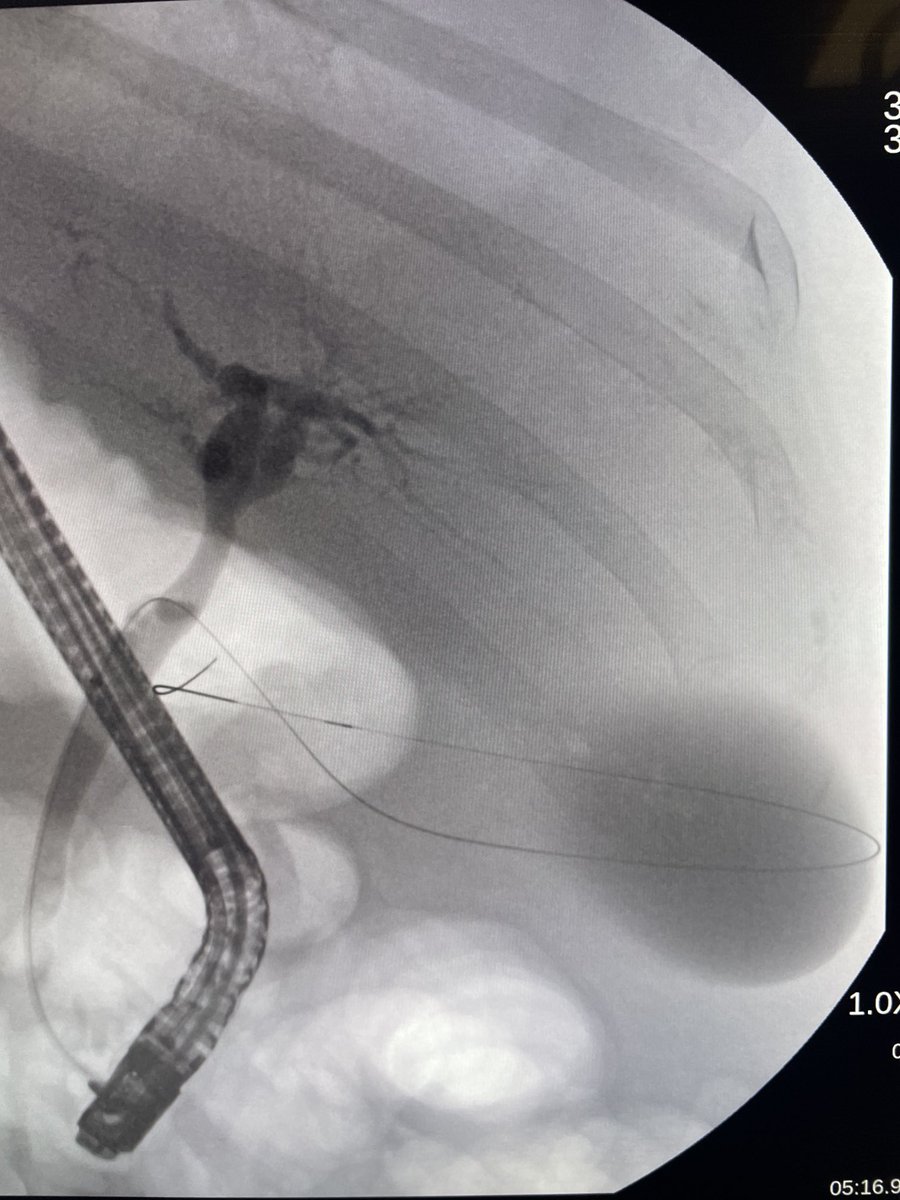

Another one. End stage liver disease with profound decompensation. Large ascites and severe coagulopathy. Acute cholecystitis treated with ERCP transcystic stent to very good effect. #gitwitter #liver #surgery @Stentingwoman ⁦@EUSandEndoscopy⁩